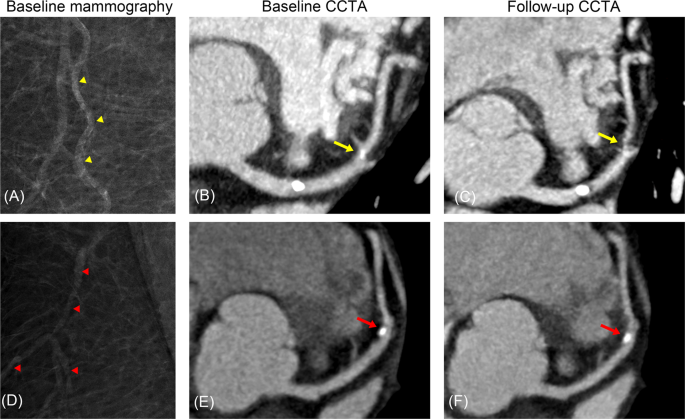

Women with BAC were more likely to have CAC at both baseline (55.6% vs. 15.7%; p < 0.001) and follow-up (77.8% vs. 29.6%; p < 0.001) than were women without BAC. Similarly, CAP was more frequently observed in women with BAC at both baseline (72.2% vs. 24.1%; p < 0.001) and follow-up (83.3% vs. 33.3%; p < 0.001). The CACS, SSS, and CAC and CAP progression rates stratified by BAC presence are shown in Fig. 2. CACS and SSS were significantly higher in women with BAC than in women without BAC at both baseline and follow-up. The progression rates of CAC and CAP were also higher in women with BAC than in women without BAC. The cumulative proportions of CAC and CAP progression stratified by BAC presence are shown in Fig. 3. Women with BAC at baseline had a significantly higher chance of CAC and CAP progression compared to that in women without BAC. Representative cases are shown in Fig. 4.

Representative cases. A 63-year-old asymptomatic woman with a BAC score of 5 (yellow arrow heads) on screening mammography (A) demonstrated calcified plaque without significant stenosis (percent diameter stenosis, 10–20%) at the proximal LAD and mixed plaque (percent diameter stenosis, 10–20%) at the mid LAD (yellow arrow). (B) Three years later, she was referred to the emergency department with chest pain and underwent CCTA, which demonstrated progression of the mid LAD lesion (percent diameter stenosis, 90%; yellow arrow). (C) Invasive angiography also demonstrated the tight stenosis of the mid LAD (percent diameter stenosis, 90%) and percutaneous coronary intervention was performed. A 51-year-old asymptomatic woman without evidence of BAC (red arrow heads) on screening mammography (D) demonstrated calcified plaque (percent diameter stenosis, 30%) at the mid LAD (red arrow). (E) Five years later, she visited the outpatient clinic due to epigastric pain and underwent CCTA, which demonstrated no change in the mid LAD lesion (red arrow). (F) BAC, breast arterial calcification; CCTA, coronary computed tomographic angiography; LAD, left anterior descending artery.